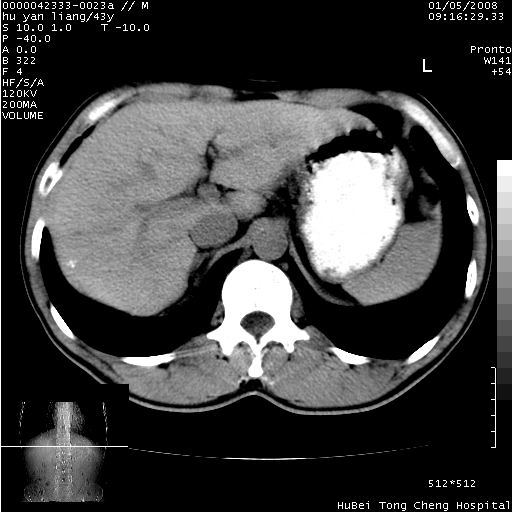

患者 男,43岁。右上腹不适1年余。既往有“肝右叶肝脓肿”病史,经保守治疗后痊愈。

b超提示:1)肝右叶肝内胆管结石。2)肝右叶占位性病变待排。

上中腹部ct轴位平扫+增强扫描(层厚10mm,螺距1.0,重建间隔10mm),图像如下:

肝右上叶偏后方较大团片状钙化灶,支持:肝脓肿后遗改变!

肝右叶后段团块状钙化灶,结合病史考虑肝脓肿痊愈后表现。